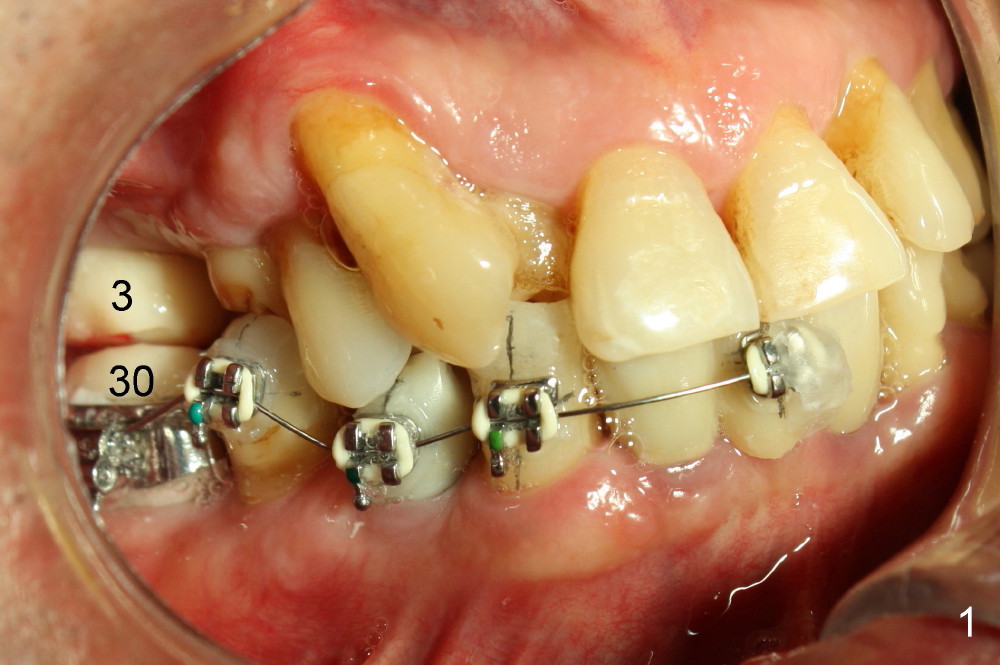

The main purpose of the 1st stage of ortho is to intrude the tooth #29 using implants at the sites of #28,30 as anchorages (Fig.1,2). If possible, intrusion of #27 is also needed. Since #24-26 is an implant supported bridge, one bracket in the pontic appears to be sufficient (Fig.2). Bracketing is also planned to extend to the lower left until #21 to distalize #22 (Fig.3). Supraeruption of #12 blocks the distalization. It appears that the supraeruption should be corrected after #13 implant placement (using the latter as an anchorage).

The bracket at the site of #25 is lost when the patient has the first meal. The rest of brackets are dislodge in a few days. This 66-year-old man does not want to pursue the ortho treatment. We are in dilemma.